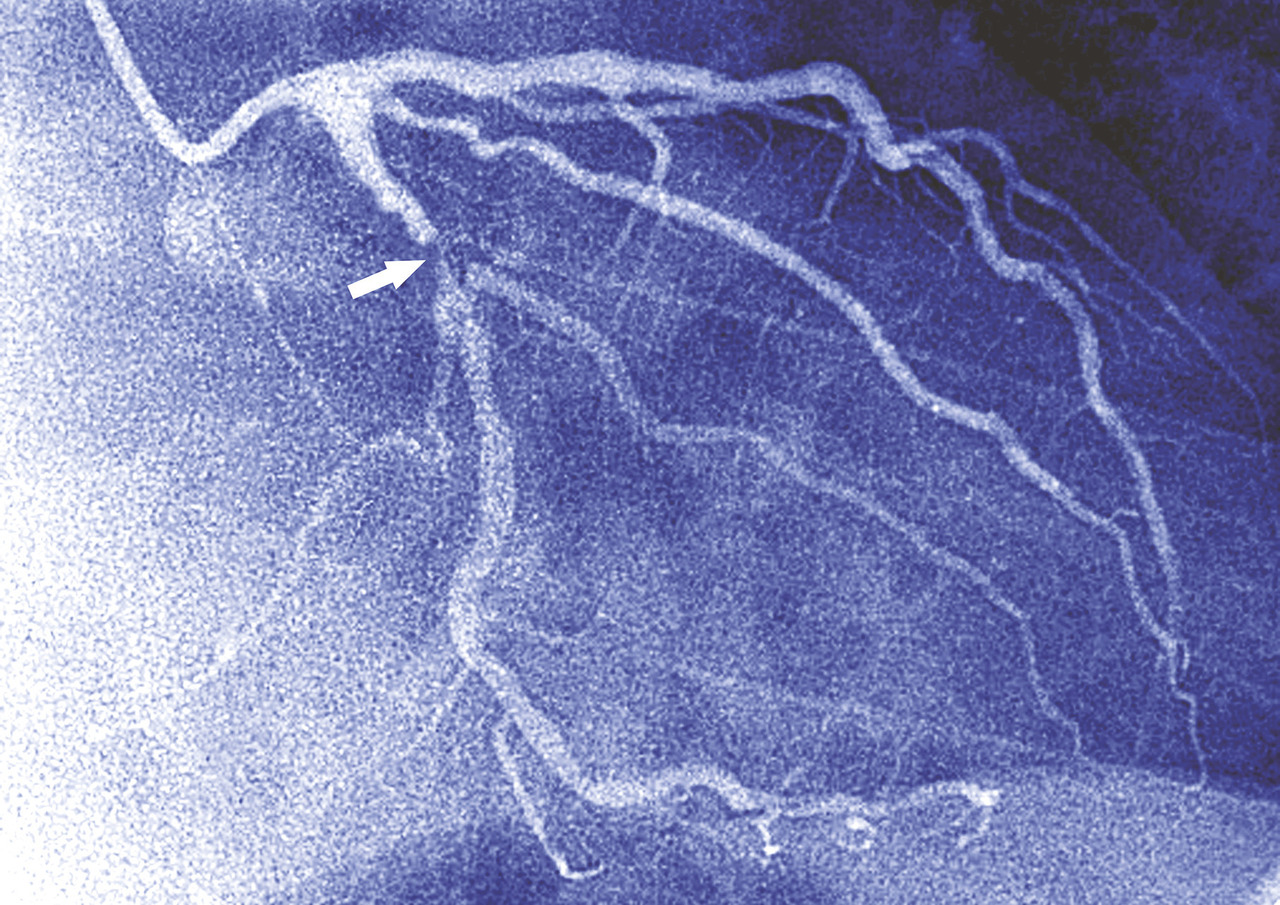

La preuve de l’efficacité indiscutable de l’aspirine pour traiter la maladie coronaire est arrivée avec l’étude ISIS-2.1 Cette étude a comparé quatre traitements chez des patients ayant un infarctus aigu : pas de traitement ; aspirine ; thrombolyse ; aspirine et thrombolyse. Les résultats sont présentés dans la figure 1 : l’aspirine diminue de plus de 20 % la mortalité – autant que la thrombolyse seule. L’association aspirine et thrombolyse fait chuter de 40 % la mortalité. Depuis les résultats de l’étude ISIS-2, l’aspirine fait partie du traitement systématique des patients coronariens en prévention secondaire. Une méta-analyse de 2002 montre que l’aspirine diminue d’environ 20 % les événements graves chez les coronariens en prévention secondaire.2 Elle constitue donc un traitement de référence de la maladie coronaire et est à ce titre irremplaçable. D’ailleurs, toutes les études concernant la maladie coronaire sont effectuées avec l’aspirine comme base de traitement.